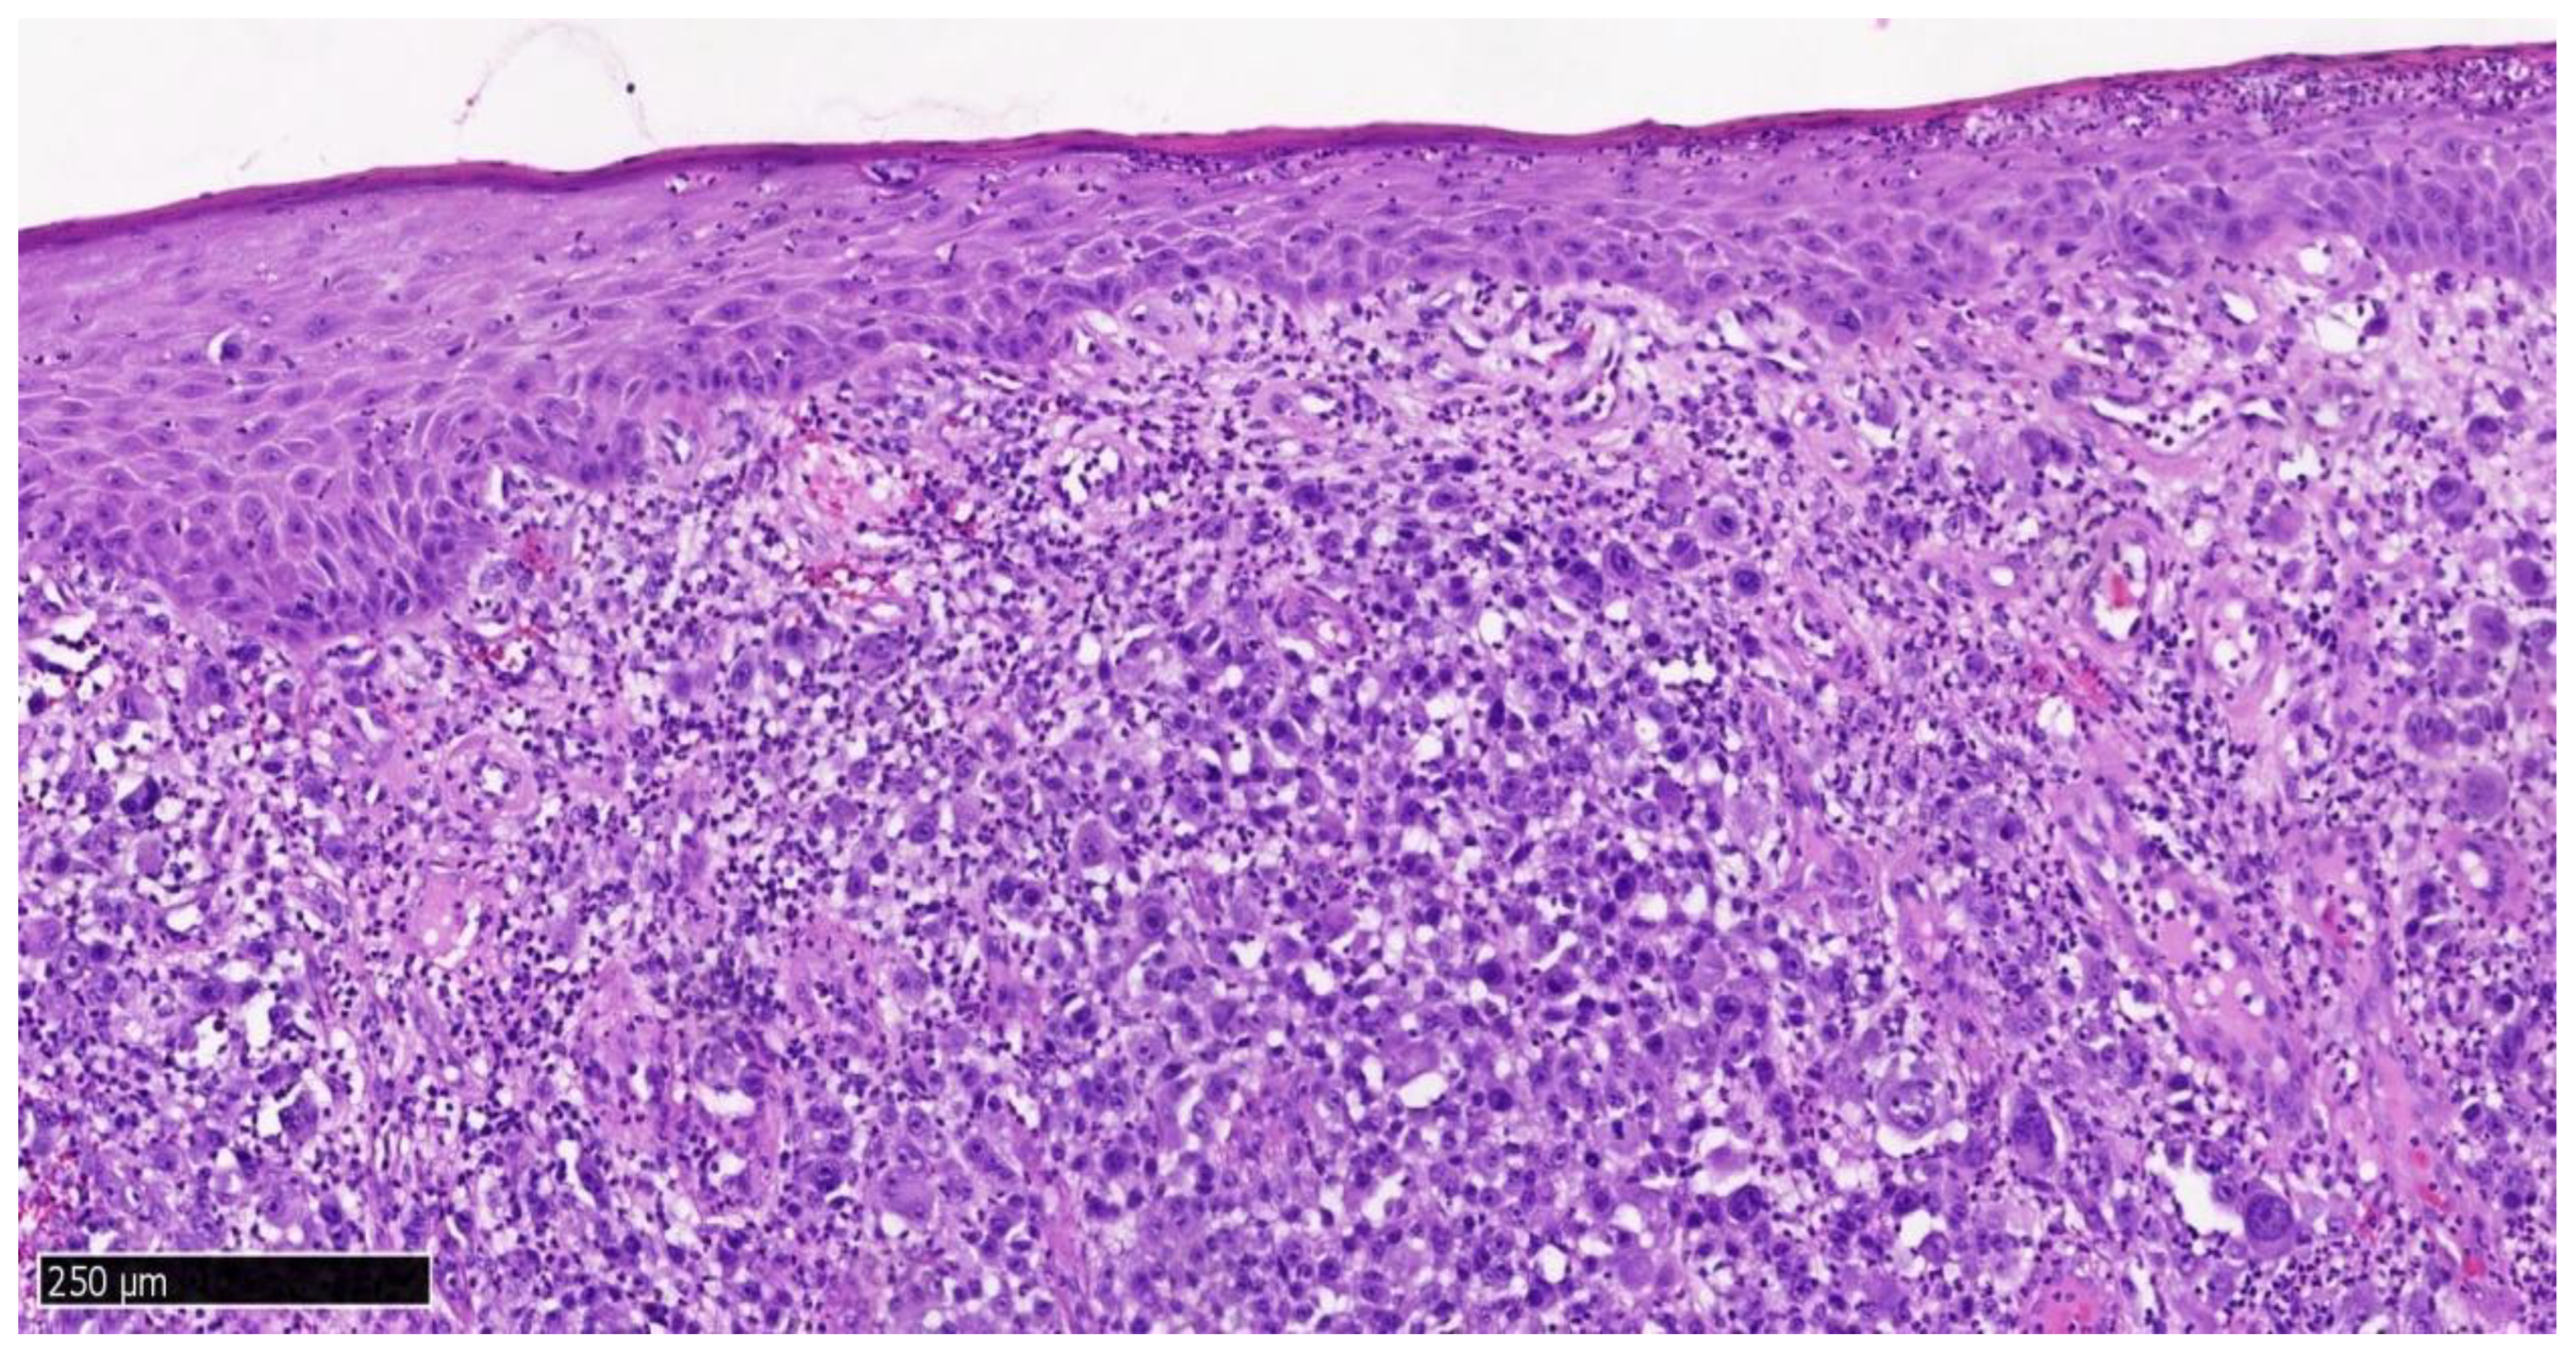

| Step 5: Histopathological and Immunohistochemical Analysis | |

| Standard H&E staining. | |

| Immunohistochemistry: S100, SOX10, HMB45, Melan-A, Ki-67. | |